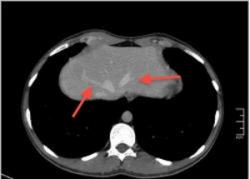

Уважаемый v1tal! Огромная Вам благодарность; Вы назвали ключевое слово: фаза! Высказанная Вами мысль, это моя основная цель данной публикации. Постараюсь позже более детально объяснить почему. Представленные сканы выше, были выполнены на стандартной портальное фазе. А сейчас, я покажу сканы данного пациента выполненные на артериальной фазе :

Это может быть нодуллярной гиперплазией? Еще бы рубец законтрастировался в отсроченную фазу.

Да Ola la, Вы абсолютно правы; это Фокальная Нодулярная Гиперплазия печени (FNH Focal Nodular Hyperplasia). Одна из немногих гиперваскулярных опухолей печени. Наверное некоторые коллеги спросят, и зачем было изначально публиковать портальную фазу, на которой «не видно» (хотя опухоль видна, пусть и не напрямую, и Nela это доказала); и только потом показывать сканы на артериальной фазе, на которой всё «красиво и показательно». Постараюсь объяснить.